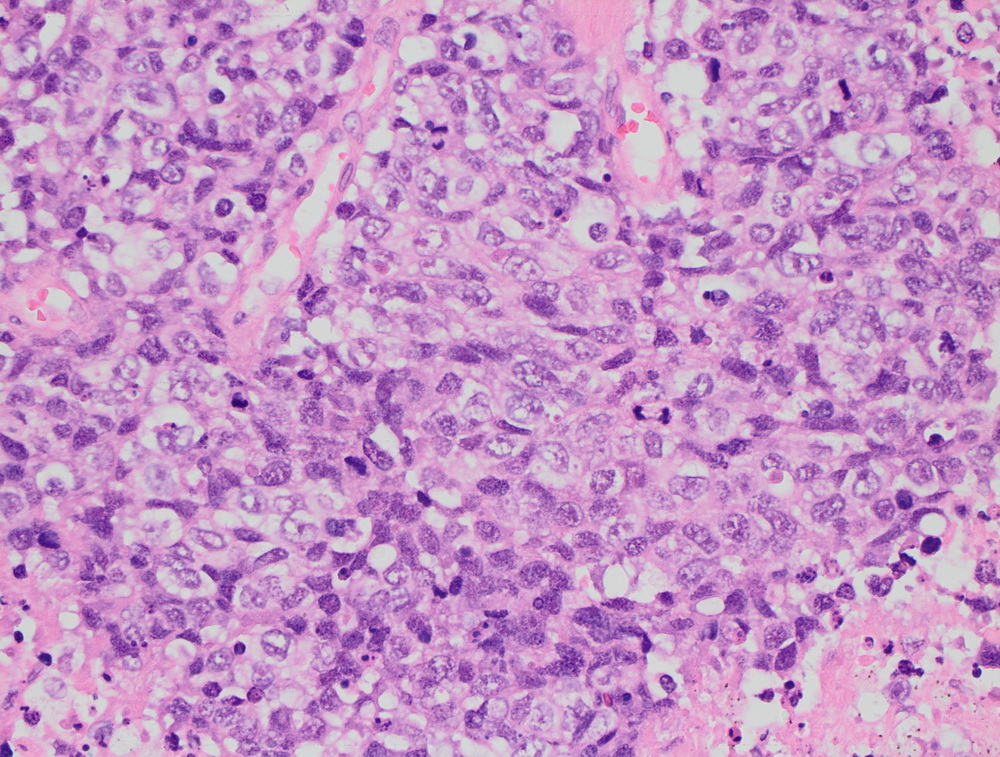

Окрашенные срезы под микроскопом

Крупноклеточная нейроэндокринная опухоль. |

МТС крупноклеточной нейроэндокринной опухоли. |